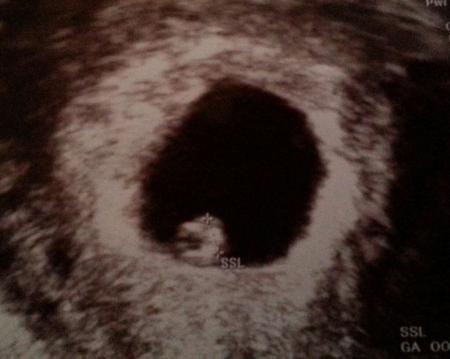

so nun will ich mich endlich mal melden. habe mich noch nicht so richtig daran gewöhnt hier stammgast zu sein obwohl ich mich tierisch freue, so ist es trotzdem irgenwie noch total unwirklich.... krümelchen ist zeitgerecht entwickelt und es ist auch tatsächlich nur eins. ich war ja sehr angespannt warum auch immer. einen schönen herzschlag durfte ich auch bewundern. in zwei wochen habe ich dann schon den nächsten termin, da bekomme ich dann den mutterpass. sämtliche blutentnahmen sind schon gelaufen bzw muss ich mir über cmv und toxoplasmose noch im klaren werden vielen dank für eure daumen und jetzt schreib ich es mal zusammenfassend hier mit rein: herzlichen glüchwunsch an die neuen kugeln alles gute für euch!!!!!!!!!

Na das sind doch mal tolle Neuigkeiten und wie schön, das du auch schon ein tolles bild bekommen hast! :) Glaub mir, wenn du erst den Mutterpass hast, gewöhnst du dich auch ganz schnell an den Gedanken hier Stammgast zu sein! :P Alles Gute weiterhin

Das sind ja gute Nachrichten am frühen morgen!!! Freue mich ganz arg für dich!!! Und ein ganz tolles Bild hast du bekommen!!! Weiter so!!!

Sehr schönes Bildchen. Freu mich über deine positiven Nachrichten. Ich habe Toxoplasmose, CMV und Liseriose gleich machen lassen. Leider muss man das ja beim FA selber zahlen. Meine Hebamme kann das alle 8 Wochen mit der Kasse abrechnen.

mich auch sehr für euch! Schönes Bildchen und auf weitere 33, komplikationsfreie Schwangerschaftswochen (O-Saft )